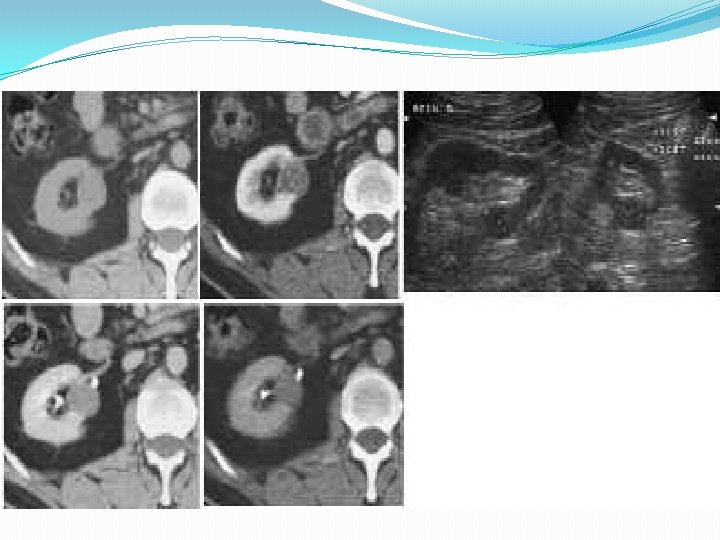

Le diagnostic de cancer du rein repose essentiellement sur l'échographie rénale et le scanner abdominal, ce dernier permettant en outre d'explorer les organes de voisinage et de faire un bilan d'extension de la tumeur. Pr michaël peyromaure dr nicolas barry delongchamps.

Le cancer du rein est la 11e forme de cancer la plus fréquente en belgique. Le cancer du rein désigne différentes tumeurs malignes. Le diagnostic de cancer du rein repose essentiellement sur l'échographie rénale et le scanner abdominal, ce dernier permettant en outre d'explorer les organes de voisinage et de faire un bilan d'extension de la tumeur.

Le traitement du cancer du rein consiste en une intervention chirurgicale, soit une néphrectomie partielle (on enlève uniquement la partie du rein malade quand la tumeur est petite et bien située) soit une néphrectomie totale (ablation de la totalité du rein atteint quand la tumeur est trop grosse ou mal. Le diagnostic de cancer du rein repose essentiellement sur l'échographie rénale et le scanner abdominal, ce dernier permettant en outre d'explorer les organes de voisinage et de faire un bilan d'extension de la tumeur. Formes asymptomatiques le cancer du rein est le plus souvent découvert fortuitement (65 %), lors d'une échographie ou d'une tdm abdominale, faites pour l'exploration de symptômes non urologiques.